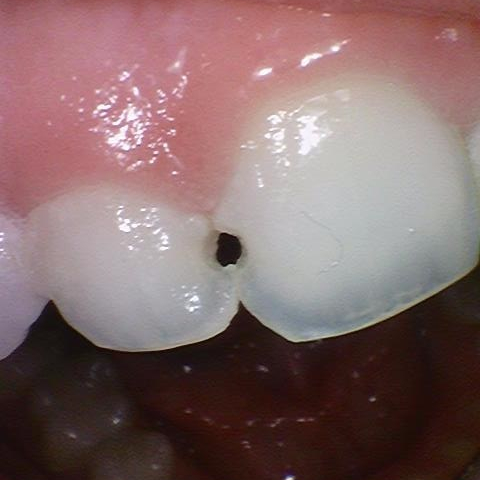

타치과 3개월된 레진이 떨어져서 치아치료 전과 후

화이트스팟을 앞니에 가지고 계신분들은 보통 컴플렉스로 잘 웃지 못하는 경우가 있습니다.

이런 경우 레진 치료로 자연스럽게 화이트스팟을 없애고 가릴 수 있습니다.